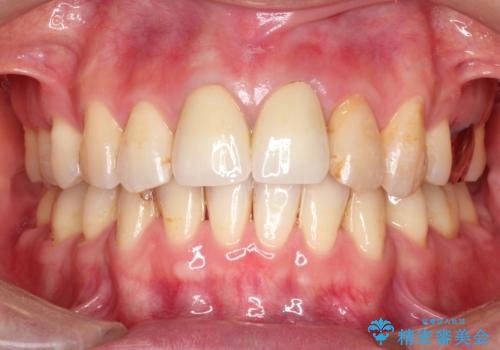

変色した前歯をセラミックできれいに レイヤリングセラミック

前歯のセラミック治療では、他の歯と色調をそろえるのが非常に難しいです。

他の歯に亀裂や白濁など複雑な色合いがある場合、それらをセラミックで再現することも可能ですが、スタンダードのオールセラミックではある程度の同調となります。

かぶせ物の種類: PFZ standard